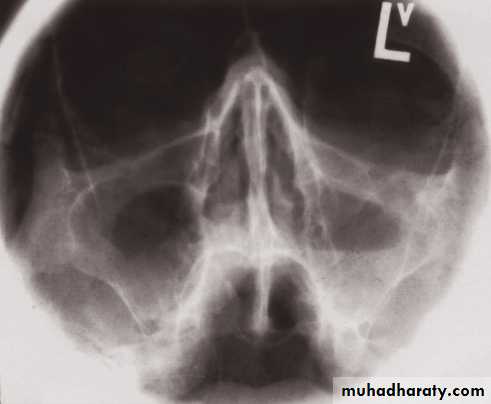

• On plain radiographs the normal sinuses are transradiant because they contain air.• Plain films have a role in showing mucosal thickening, fluid levels, bone destruction and fractures.

• The causes of an opaque sinus are:

• Infection or allergy.

• Mucocele.

• Carcinoma of the sinus or nasal cavity.

Mucosal thickening and a fluid level